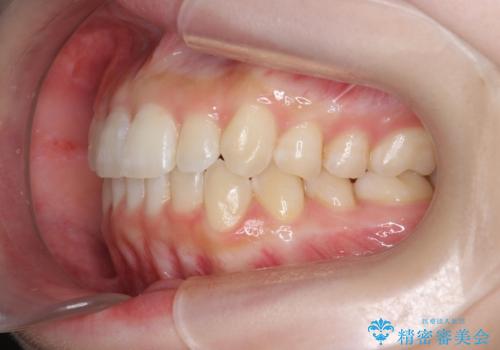

前歯のねじれを治したい マウスピース矯正治療

- 前歯のねじれを改善し、きれいな歯並びにしたい!と矯正治療を希望され来院されました。

マウスピース矯正システム、インビザラインのシミュレーションを用いて最終的な歯の位置をしっかりと確認したのち、きれいな歯並びとなるようマウスピース矯正治療を開始します。

ねじれとともに突き出たように見えていた前歯も見た目が大きく改善し、喜んでいただくことができました。